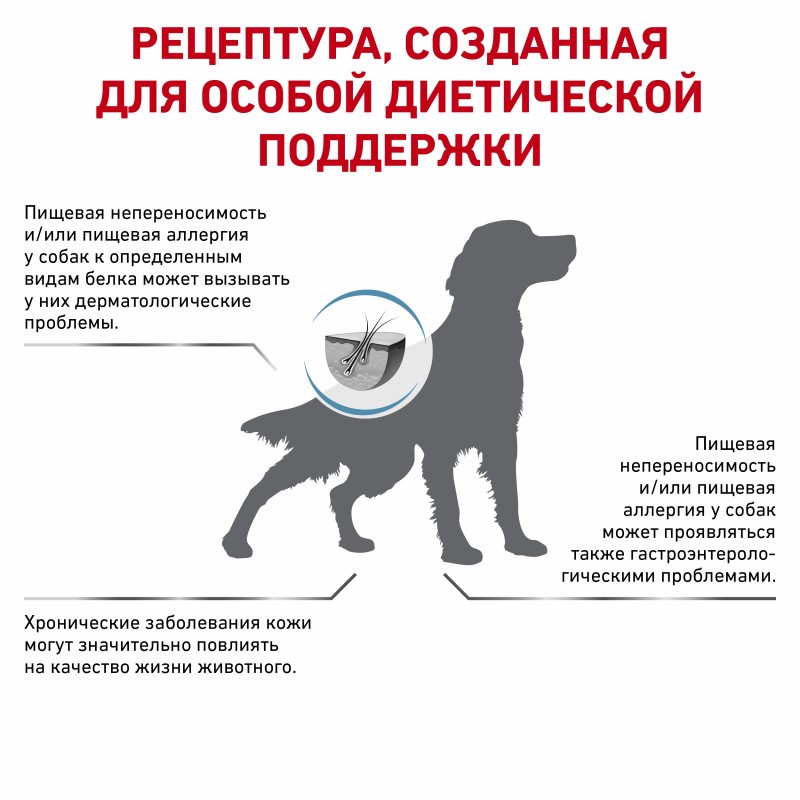

Диета для собак весом больше 10 кг с пищевой аллергией или непереносимостью.

ПОКАЗАНИЯ

- Нежелательная реакция на корм

- Воспалительные заболевания кишечника

- Атопический дерматит в сочетании с хроническим зудом

- Экзокринная недостаточность поджелудочной железы

- Хроническая диарея

- Пролиферация бактерий в тонком кишечнике (SIBO)